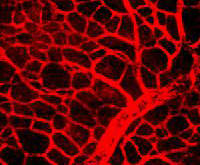

Используя МРТ и нанотехнологии, ученые из Йельского университета создали способ наблюдения за ростом выращенных в лаборатории сосудов после того, как они были имплантированы в организм пациентов.

Ученые использовали две различные группы клеток, выращивая кровеносные сосуды. В первой группе клетки были помечены контрастным веществом для МРТ, во второй были обычные клетки. Все клетки были использованы для выращивания кровеносных сосудов и имплантации мышам. Цель состояла в том, чтобы отследить рост новых кровеносных сосудов с помощью МРТ и убедиться, что добавление контрастного вещества не влияет на клетки.

Исследователям удалось с помощью МРТ уивдеть клетки, помеченные контрастным веществом.